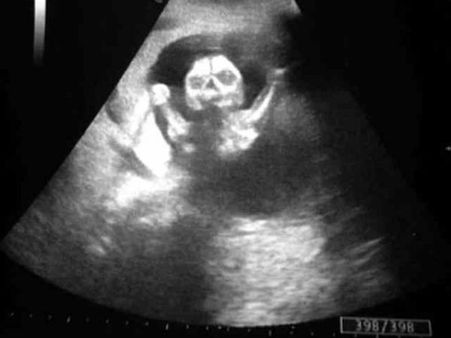

Picture#5 The Skeleton Baby!

This can freak us to the core, but it raises the question of the ultrasound being real or fake! What do you think? Is the picture real of fake? Keep reading and go ahead and check the next one...